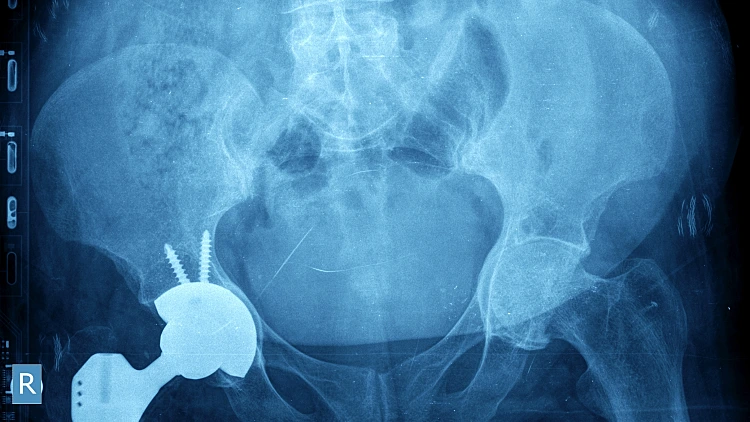

צילום רנטגן של מפרק ירך

צילום רנטגן של מפרק ירך | צילום: פוטוליה